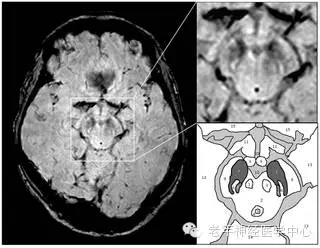

2013年,研究人员发现了一种新的帕金森病生物指标,称为Nigrosome,其不仅可用于诊断病情,同时也无形中追踪病情的发展。“The ‘Swallow Tail’ Appearance of the Healthy Nigrosome – A New Accurate Test of Parkinson’s Disease: A Case-Control and Retrospective Cross-Sectional MRI Study at 3T”描述了这种成像标志的缺席如何可以帮助诊断帕金森病。

利用高分辨率的超高场7T磁共振成像,诺丁汉研究小组已经找到了帕金森病的病理特点,在中脑一个小区域(黑质体substantia nigra)的结构变化。最新的研究表明,利用全国各地医院都有的3T磁共振成像技术也能检测这些变化。随后,他们创造了短语“燕尾状外观”作为健康黑质体的一种易于识别的标志,而黑质体在帕金森病中是缺失的。研究人员回顾了总共114个高分辨率扫描,在94%的例子中,利用这种技术能够做出精确诊断。

“使用磁共振成像(没有电离辐射,并且比核医学技术便宜很多),我们可以确定一种特殊的影像特征,它与燕子的尾巴形状非常相似,因此我们将其称为‘燕尾征’。在帕金森病中缺乏这种标志。”